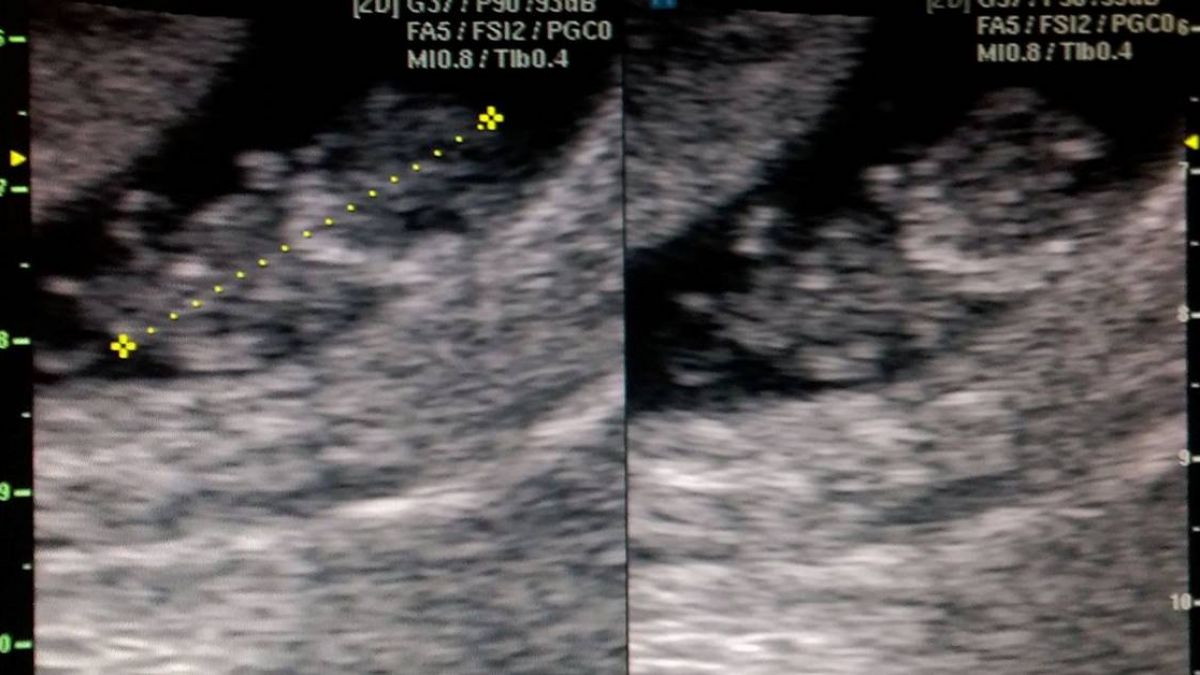

▲「二寶」的超音波照。(圖/百吻巴黎Kiss.Paris-楊雅晴臉書)

百吻巴黎楊雅晴在臉書專頁PO出「二寶」的超音波照片,秀出寶貝9周大的模樣,從照片中可以清楚看到「二寶」的身形,她感到敬佩的說「這是閃過保險套百分之九十幾的網羅的神嬰,咪哈要當姊姊了。」還說「二寶看來也是狠角色」、「硬要來!」